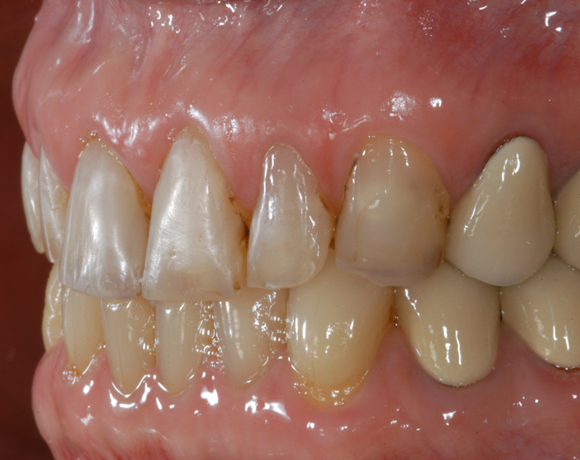

22 Einzelkronen mit Eris for E II

Empress II Presskeramik mit Eris Verblendkeramik bei einer Neuversorgung im Oberkiefer komplett und im Unterkiefer Vollkronen auf den Seitenzähnen.

Ein Projekt aus dem Jahr 2004

Hier wurden der ganze Oberkiefer und die Seitenzähne im Unterkiefer mit neuen Kronen aus Empress 2 und mit Eris Verblendkeramik versorgt.